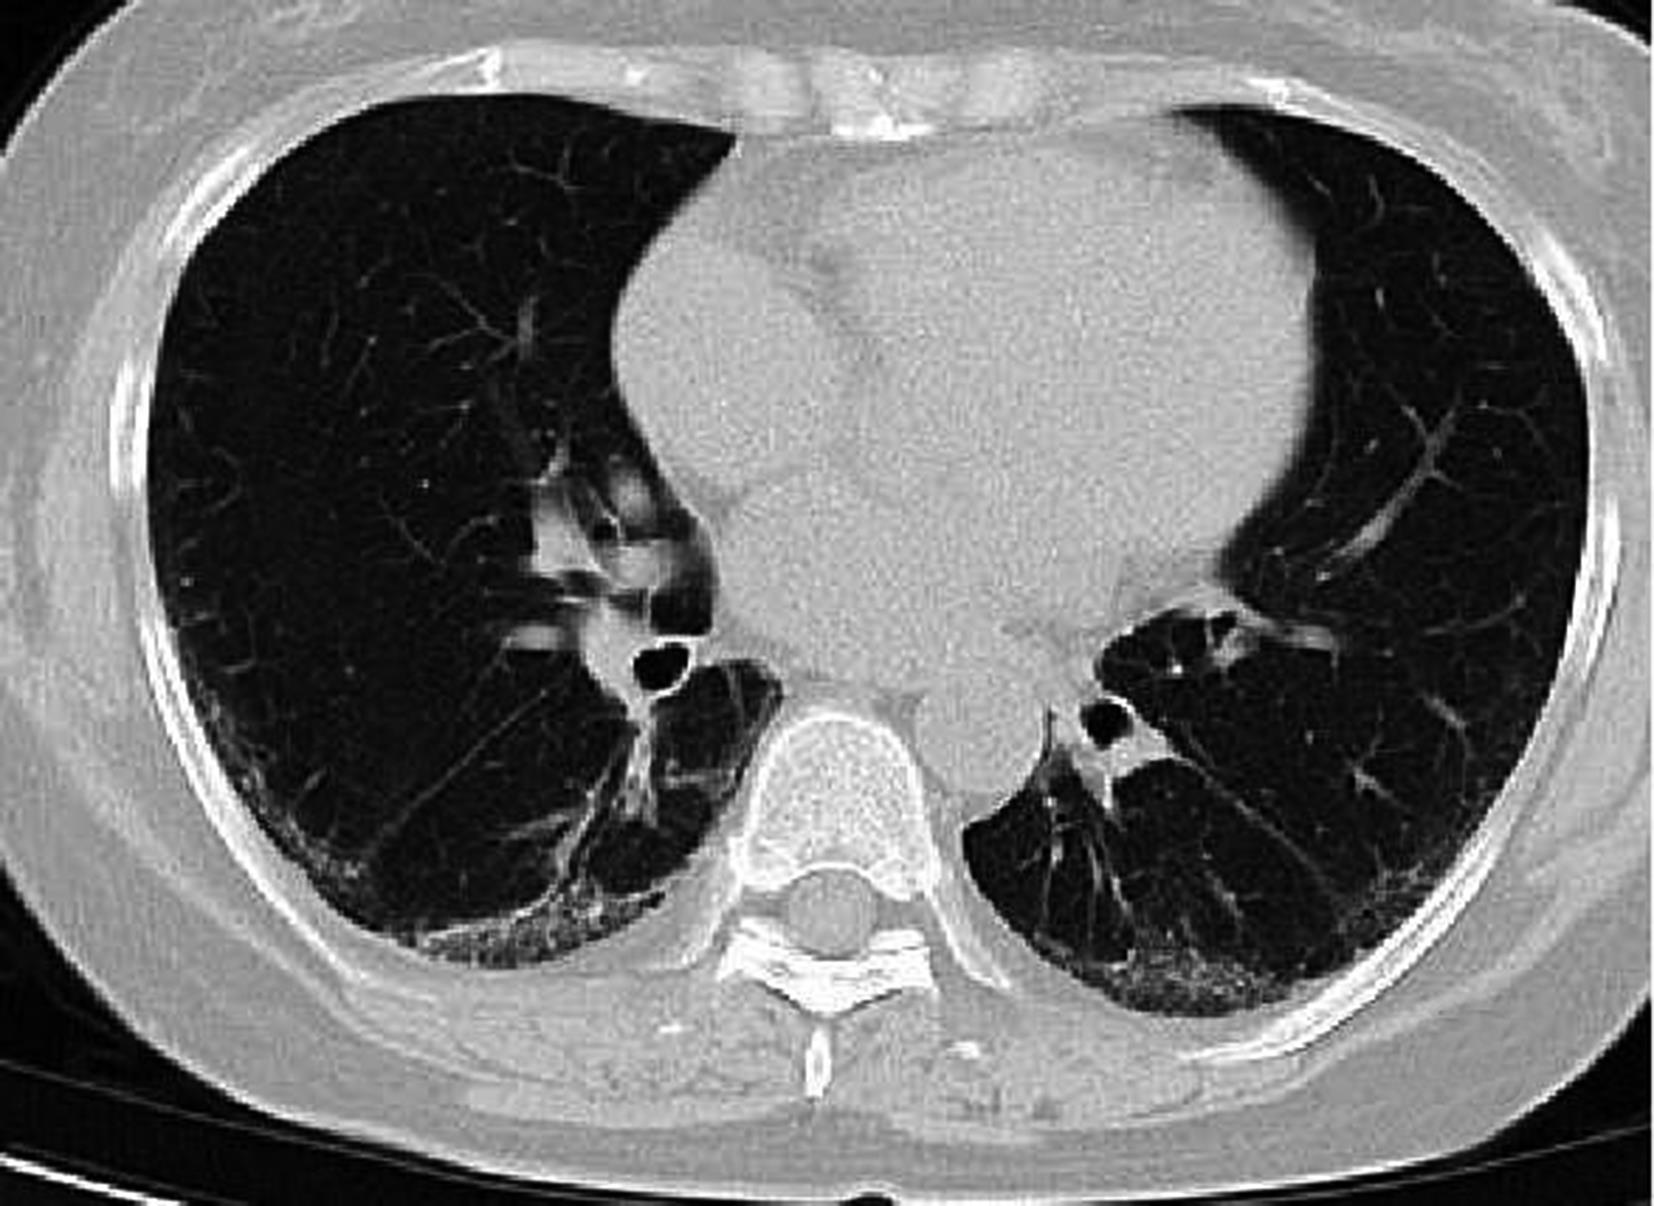

• 系统性红斑狼疮患者肺部影像学特征与疾病活动度相关性研究

2023, 48(11):1351-1355. DOI: 10.13406/j.cnki.cyxb.003353

摘要 (94) HTML (39) PDF 1.35 M (174) 评论 (0) 收藏

摘要:目的 探讨系统性红斑狼疮合并间质性肺病的CT特征与疾病活动度的相关性。方法 纳入131例系统性红斑狼疮相关间质性肺病患者。分析其疾病活动度评分、影像学特征及高分辨CT(high resolution computed tomography,HRCT)肺间质纤维化Kazerooni评分。采用Spearman秩和相关系数检验分析各评分之间的相关性。结果 Kazerooni评分法中的磨玻璃评分与系统性红斑狼疮疾病活动度-2000评分(systemic lupus erythematosus disease activity index-2000,SLEDAI-2000)呈正相关,差异有统计学意义(rs=0.388,P<0.001)。而纤维化评分与SLEDAI-2000评分之间差异无统计学意义(P=0.837)。弥漫性肺泡损伤(diffuse alveolar damage,DAD)组磨玻璃评分得分最高,寻常型间质性肺炎(usual interstitial pneumonia,UIP)组纤维化评分得分最高,差异有统计学意义(均P<0.001)。比较不同间质性肺病(interstitial lung disease,ILD)类型之间SLEDAI-2000评分差异无统计学意义(P>0.05)。结论 胸部HRCT可有助于更全面地评估系统性红斑狼疮疾病情况,对制定治疗方案具有重要意义。